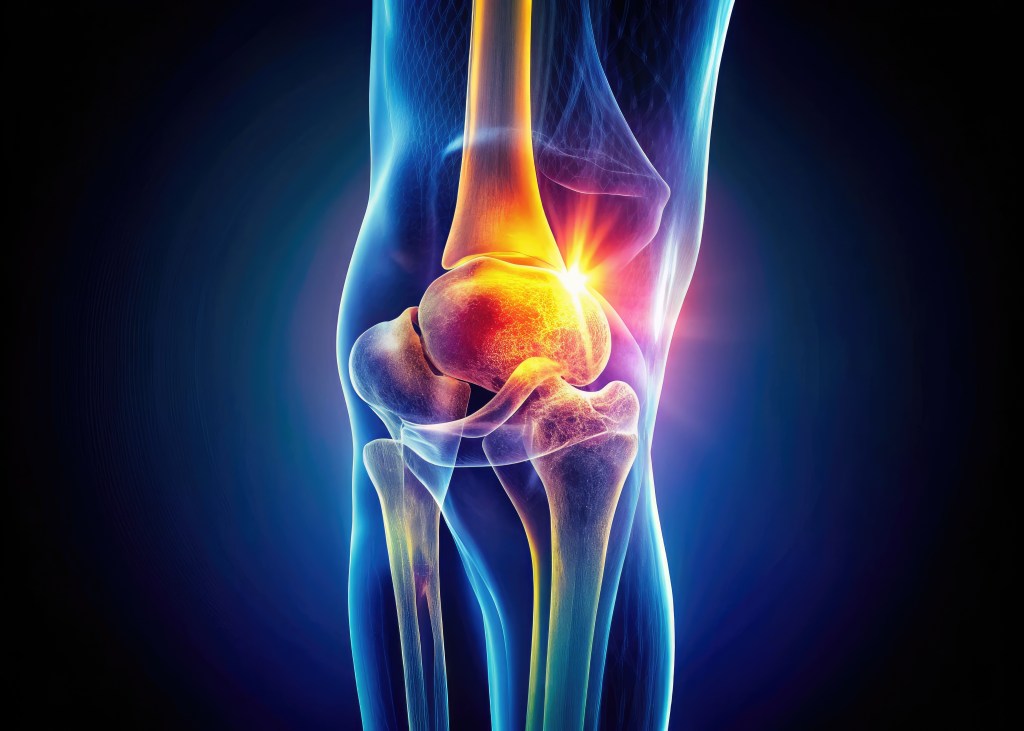

Εξειδικεύεται στην ολική αρθροπλαστική ισχίου, γόνατος και ώμου, καθώς και στην αρθροσκόπηση αθλητικών κακώσεων, εφαρμόζοντας ελάχιστα επεμβατικές τεχνικές που προσφέρουν άμεση ανακούφιση και ταχεία αποκατάσταση των ασθενών.

Αθλητικές κακώσεις

Αποκατάσταση ρήξεως χιαστού συνδέσμου γόνατος και μηνίσκου (One Day Surgery)

Οστεοπόρωση και oστεοαρθρίτιδα